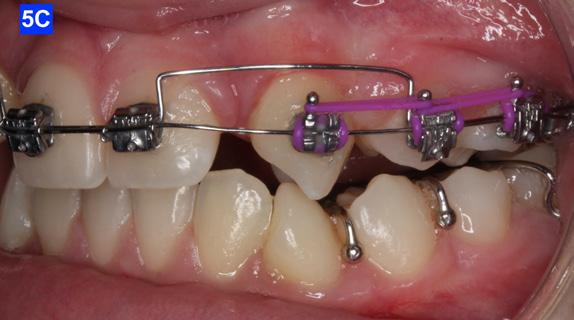

The eruption of maxillary cuspids was expedited with the Adrian “U” bend spring5 where the cardinal arch wire was a .016 SS and the secondary arch wire a .014 NiTi5. Since we were working with the PSL brackets, a combination of larger diameter wires would not allow the latch to close (Figure 5–A, B, C). Also note the progress in retraction of the lateral incisors (Figure 5-D).

Figure 5A: Adrian “U” bend spring, frontal view Figure 5B: Adrian “U” bend spring, right lateral view Figure 5C: Adrian “U” bend spring, left lateral view Figure 5D: Continuation of retraction, occlusal view Figure 6A: OCS between the central incisors an the cuspids Figure 6B: Retraction of the lateral incisors is completed Figure 7A: Starting treatment on the mandibular arch, frontal view